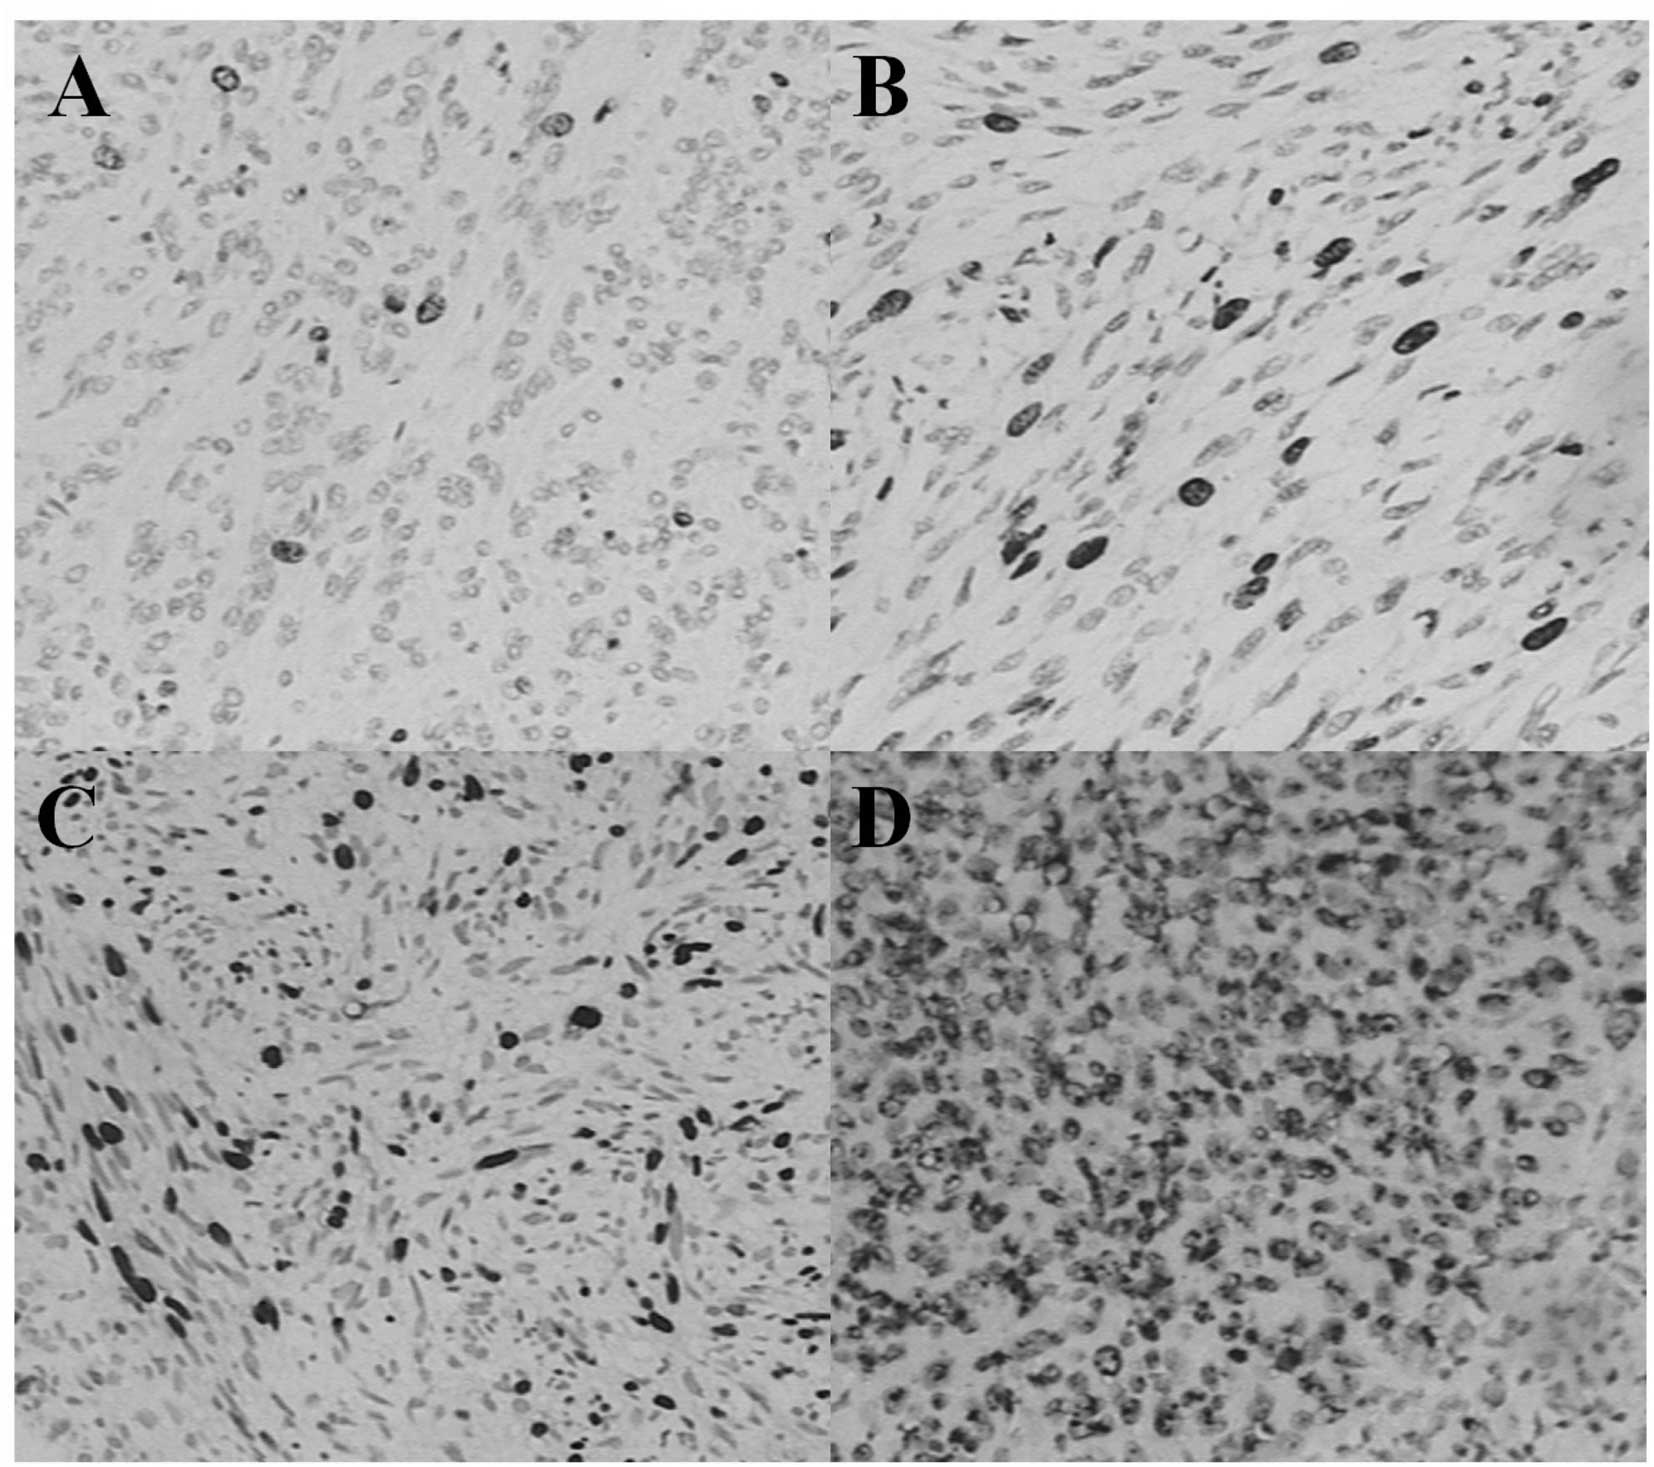

A total of 49 GIST patients (28 men and 21 women) underwent surgical resection for GISTs. Patients ranged in age from 29 to 84 years (mean, 63.3±11.8; median, 60). The tumors were located in the stomach (34 cases, 69%), small intestine (11 cases, 22%), large intestine (1 case, 2%), omentum (1 case, 2%), enterocoelia (1 case, 2%) and rectum (1 case, 2%). The tumors varied between 0.2 and 32.0 cm (mean: 12.7 ± 8.4; median: 5.0) in size. Histologically, 13 tumors were of the spindle-cell type, seven tumors were of the epithelioid-cell type and the remaining 29 were of the mixed spindle- and epithelioid-cell type (Fig. 1). Mitotic counts in 24 cases were less than 5 per 50 high power field (HPF; 49%), 13 were 5–10 per 50 HPF (27%) and 12 were more than 10 per 50 HPF (24%; Fig. 2). Ki-67 LI was classified as ‘−’ in 21 cases (43%), ‘+’ in 15 cases (31%), ‘++’ in four cases (8%) and ‘+++’ in nine cases (18%) according to the previous evaluation standards. According to the risk-grading system, one case was classified as very low grade (2%), eight cases were classified as low grade (16%), 22 as intermediate grade (45%) and 18 as high grade (37%; Fig. 3). The clinicopathological findings of the GISTs and major clinical symptoms are summarized in Table I.

Figure 3.

Immunohistochemical staining for Ki-67 IL (A,B,C,D). (A) GISTs showing ‘−’ Ki-67 scale (less than 5%). (B) GISTs showing ‘+’ Ki-67 scale (5–10%). (C) GISTs showing ‘++’ Ki-67 scale (10–15%). (D) GISTs showing ‘+++’ Ki-67 scale (>15%). GISTs, gastrointestinal stromal tumors.